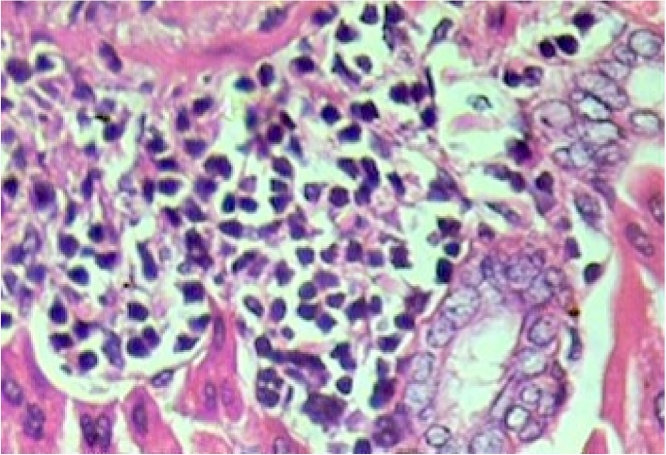

Histopathological evaluation of the animal organs: the heart and kidneys presented no particularities. Yet histopathological examination of the lungs (Fig. 5), and liver (Fig. 1, Fig. 2, Fig. 3, Fig. 4) presented significant though minor changes. In both sexes, a microscopic study of the lungs (Fig. 5) presented lobular parenchymal architecture with well distributed bronchial and bronchiolar elements. The alveolar tissue was represented by thin walled alveolar structures, exhibiting normal pneumocyte covering; the septal matrix was both lacking and weak, with congested capillaries, without, however, a sign of recent or older hemorrhages. In the peri-bronchial connective tissue, the presence of follicular, non-encapsulated lymphoid aggregates was found in close association with peri-bronchial venules and with the bronchiolar mucosa, and represented evidence of regular local BALT (bronchi associated lymphoid tissue) connections. Finally, in the samples analyzed, no atypical epithelial cell stigmas were observed. With regard to the histological liver study (Fig. 1, Fig. 2, Fig. 3, Fig. 4), preservation of the lobular architecture was observed with regular distribution of vascular-biliary atresia, and terminal hepatic vein portal triads in all samples. The portal spaces were host to a mild focally distributed lymphocytic influx. In four of the six animals in this study, an occurrence of small and isolated outbreaks of hepato-cytolysis (lobular necrosis) associated with exudation of mononuclear cells was noted. Signs of mild reactivity were represented by Kupffer cell hyperplasia. In addition, the presence of venule and sinusoidal congestion, in discreet degrees in zone 3 was observed. Although all tissues have some ability to metabolize drugs, the liver is the main organ that performs this function, and probably due to this factor, the liver is the organ most affected by the toxic effects of certain substances, even though they affect all systems and organs [29]. The results of this study demonstrate that the hydroalcoholic extract of the leaves of Cissus sicyoides, does not present chronic non-clinical toxicological effects at the popular dose of 4.5 mg/kg.

Fig. 1.

Liver – Focus of hepatocellular necrosis associated with the influx of lymphocytes. Reactive Kupffer cells. Hematoxylin and eosin, X400.

Fig. 2.

Liver – lobular necrosis with lymphocyte influx, in zone 3 (perivenular). Venule congestion. Hematoxylin and eosin, X400.

Fig. 3.

Liver – Portal Space - venous congestion and lymphocyte profile. Hematoxylin-eosin, X100.

Fig. 4.

Liver – Lymphocyte profile - Hematoxylin-eosin, X400.